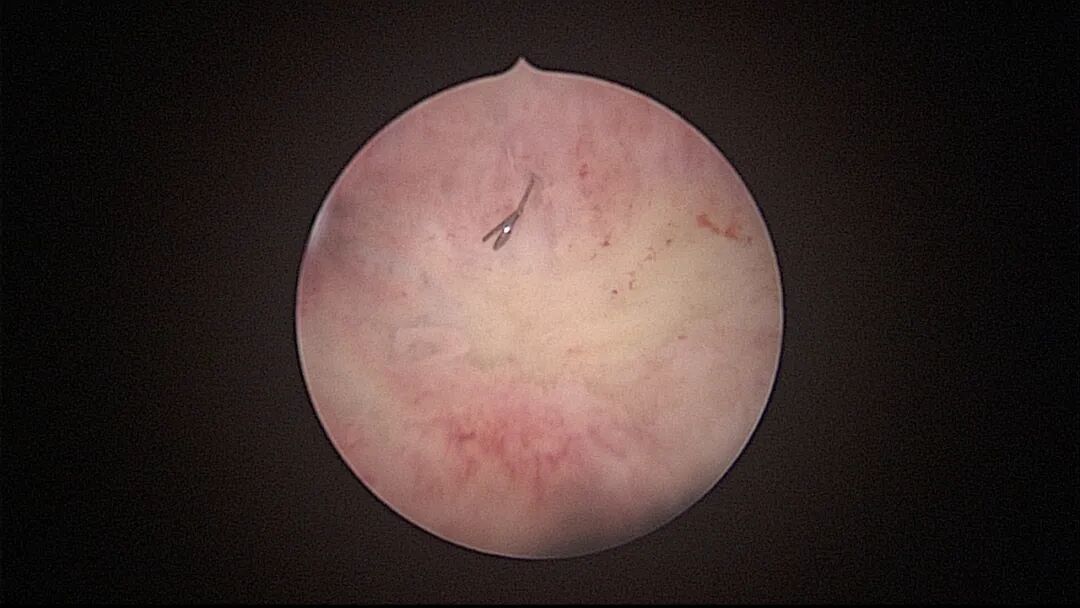

操作步骤描述:宫腔检查镜可完成操作,扩张宫颈至7号扩宫棒,检查镜能轻松通过,避免镜鞘与节育环纵臂在宫颈管形成卡压及筷子效应,影响操作,或卡压摩擦阻力大带出节育环。可用单级电针在宫底扎出小凹坑做标记或作为置入挂钩的隧道(不是必须的)。将挂钩用异物钳直视下送入宫腔,或用中弯钳盲视下送入宫腔,异物钳夹持挂钩将倒钩端插入宫底肌层,越过倒钩。用环尾丝或不可吸收线在节育环顶端打结,形成一个线圈,直径约0.5cm~1cm,结打在线圈旁边,便于夹持操作。将环装回推杆送入宫腔,再夹住节育环固定线圈抵紧宫壁稍旋转就可以将线圈滑进挂钩缺口,挂到挂钩上,可再次向宫底推送挂钩少许,不必夹闭挂钩缺口,重力作用和内膜生长都会阻止线圈脱出,可以用电针电凝挂钩周围组织,进一步防止挂钩脱落。异物钳原位固定节育环,退出宫腔镜,距宫颈外口0.5cm~1cm剪断剩余尾丝。宫颈扩张到9号扩宫棒,冷刀系统异物钳夹持挂钩及线圈也可完成以上操作。

单级电针标记挂钩位置